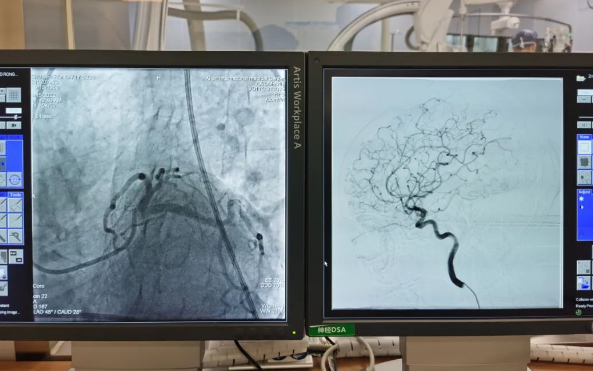

術(shù)前準(zhǔn)備就緒后,心內(nèi)二病區(qū)曾廣偉主任、高釗副主任醫(yī)師、神外科陸丹副主任醫(yī)師共同為患者行腦血管造影術(shù) 冠狀造影術(shù)。術(shù)后,朱奶奶恢復(fù)良好。